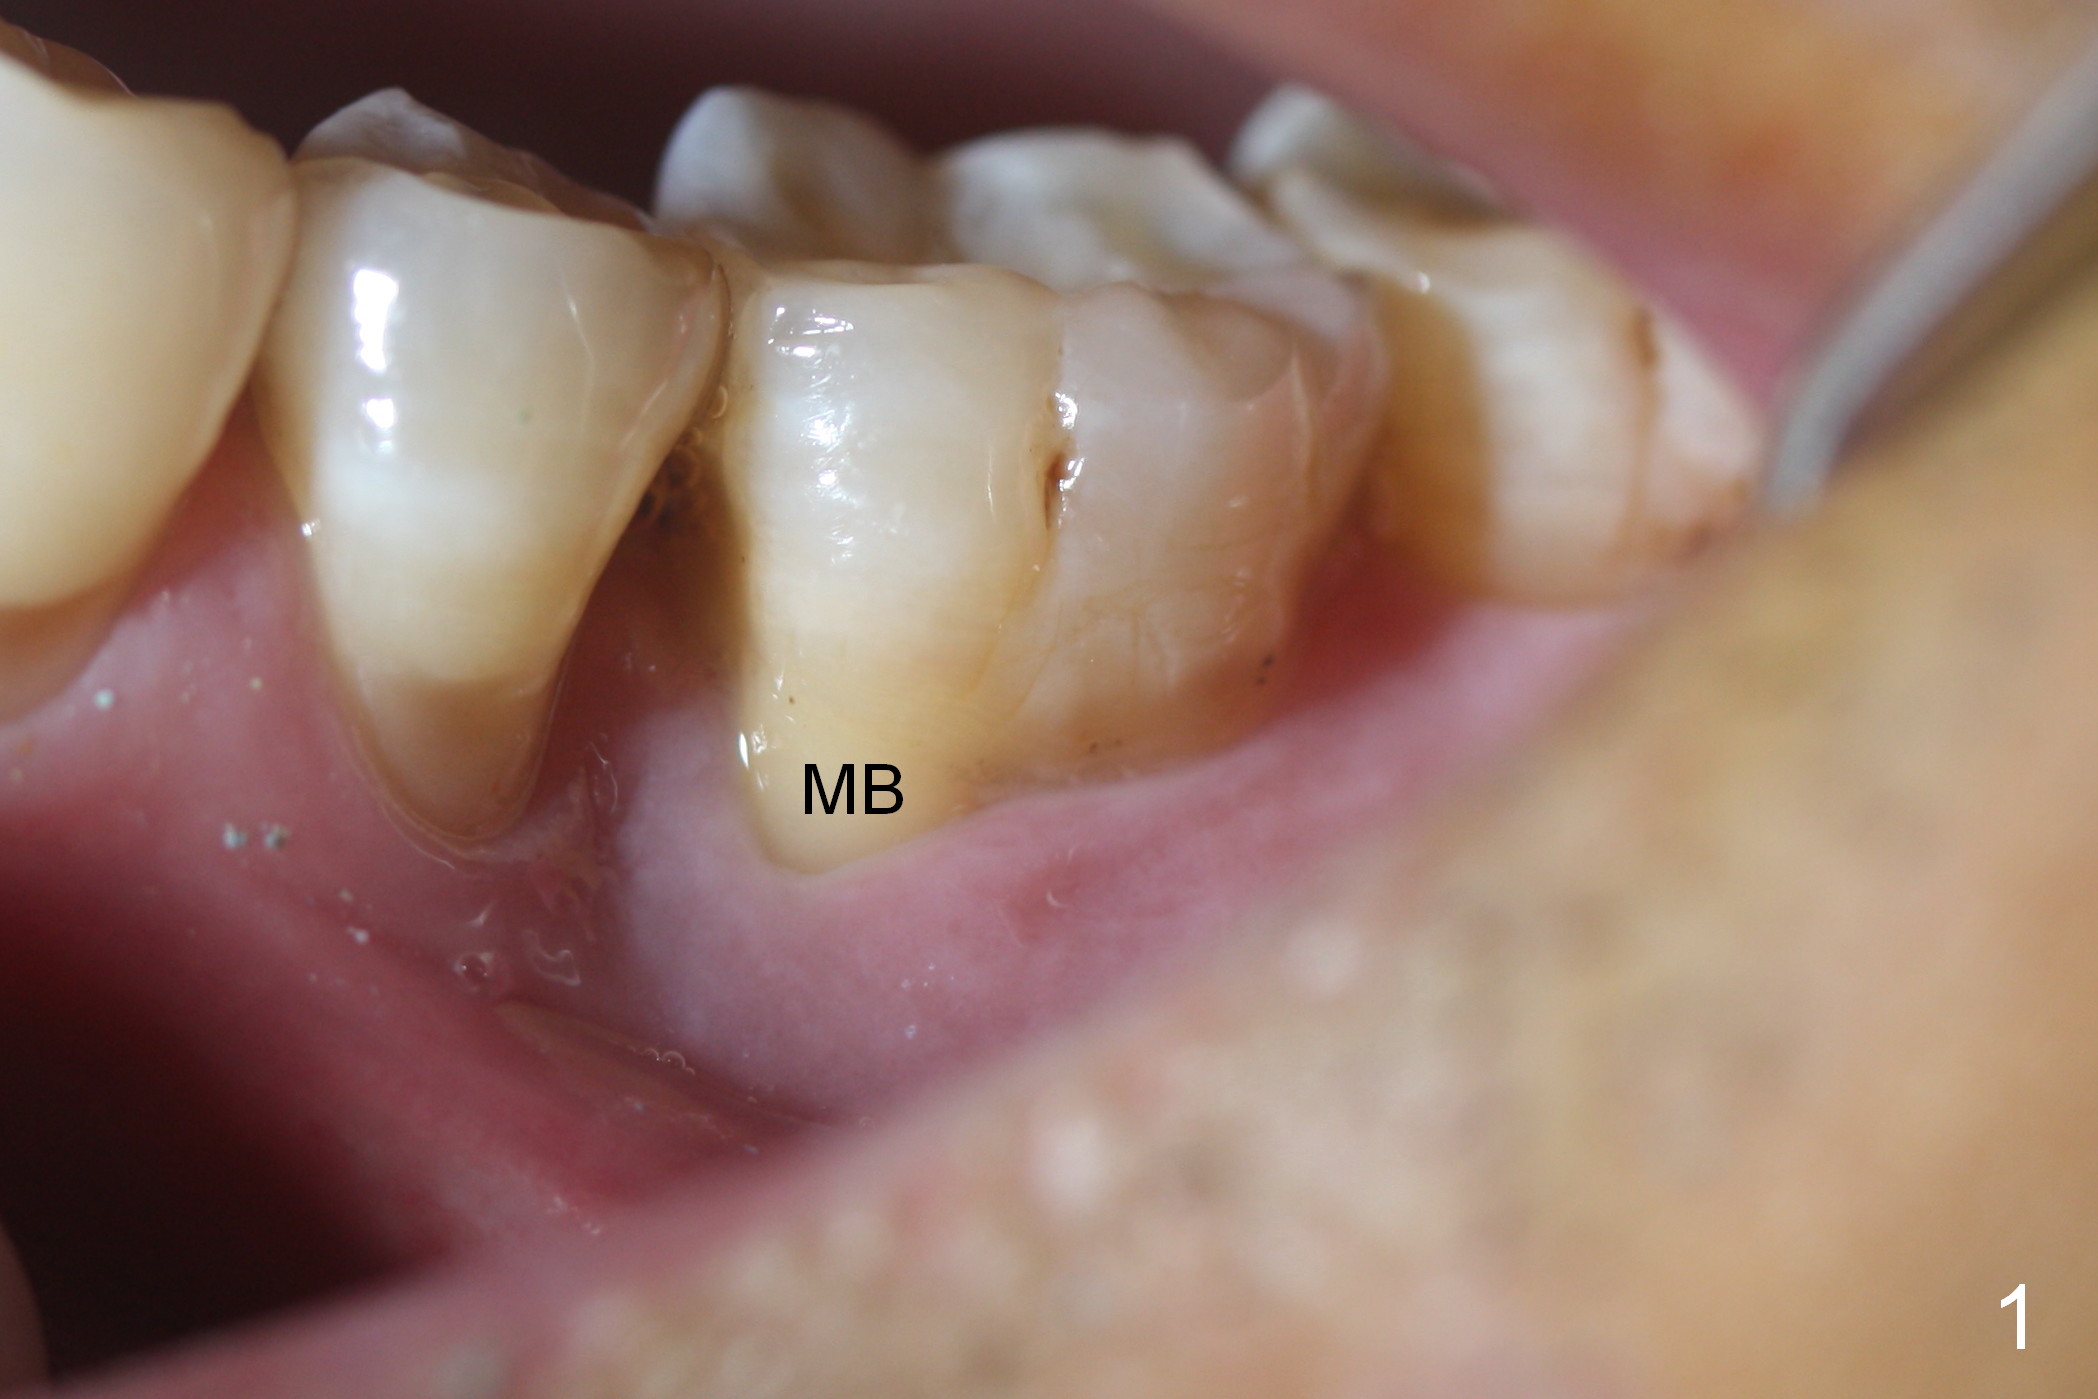

Considering the severe bone loss in the meisal socket, socket preservation is indicated if immediate implant is not feasible.  Preop exam shows that the mesiobuccal gingival recession (Fig.1 MB) is not as severe as the mesiolingual one (Fig.2 ML).  Because of oozing from the mesial socket, buccal envelop incision is made with flap raising to increase visibility.  Probably due to periodontal infection, pain control is difficult.  Osteotomy buccal to the Inferior Alveolar Canal proves to be risky.  In addition, osteotomy in the mesial socket is more difficult than the distal one (Fig.3).  Once the osteotomy depth is determined relative to the superior border of the Inferior Alveolar Canal (4 mm), the osteotomy depth increases by 2 mm.  A 5.5x10 mm implant is placed with insertion torque ~ 35 Ncm (Fig.4); a 15 ° angled abutment (5.5 mm in diameter, 4 mm in cuff) is placed mesially.  Then the abutment is turned lingually favorable for restoration (Fig.5), the remaining socket is filled with allograft/Osteogen (*) and Collagen Plug.

There is bone growth in the mesial socket 5 months post graft (Fig.10).  Use Magic Split to get access and test bone density (which must be low or medium in the upper portion).  Use drills beyond the socket if necessary.  Crown/implant ratio is unfavorable (Fig.11); so progressive loading is essential.